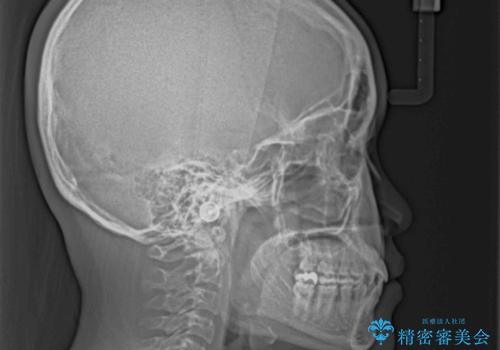

上顎の拡大に伴い反対咬合があっという間に改善されました。

元々の歯列不整は軽微であったため、僅か1年の期間で治療を終えることができました。